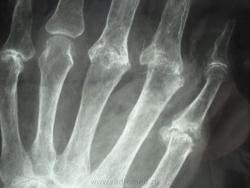

женщина,1930 г.р. , в наравлении -деформирующий артроз? В анализах повышено СОЭ, СРБ, ревмат. фактор.

Рентгенологически выделяют 4 стадии ревматоидного артрита: I стадия (начальная) — только околосуставной остеопороз; II стадия — остеопороз + сужение суставной щели; III стадия — остеопороз + сужение суставной щели + эрозии костей; IV стадия—сочетание признаков III стадии и анкилоза сустава. Раньше всего рентгенологические изменения при ревматоидном артрите появляются в суставах кистей и плюс-нефаланговых суставах.

после консультации ревматолога окружной больницы, пациентка приехала с диагнозом псориатический артрит. но продолжение этой истории следует, еще поедит на консультацию к другому специалисту, терапевт не согласен с диагнозом...

Ревматологи с областной больницы ставят DS: Ревматоидный  артрит, акт. II. R-стадия III. НФС III. Вторичный ДОА III ст. Анемия хронических заболеваний.

Без псориаза и его кожных проявлений - псориатическую артропатию диагностировать трудно...